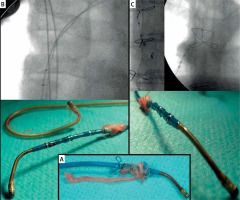

Figure 1

Extraction of CS lead designed for permanent LA pacing for atrial resynchronisation. Strongest connective tissue scar near CS ostium (around anodal ring of the lead), lack of connective tissue remnant on the anchoring strand (A) and extraction of CSO screw-in lead designed for permanent LA pacing for biatrial pacing. Entrance with Byrd dilator into proximal CS was necessary to liberate both of the electrodes from the connective tissue scar. Strongest solid scar around anodal ring of the lead (B)